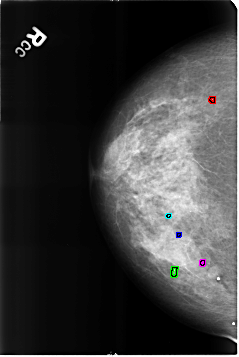

B_3227_1.RIGHT_CC

FILE: B_3227_1.RIGHT_CC.OVERLAY

TOTAL_ABNORMALITIES 5

ABNORMALITY 1

LESION_TYPE CALCIFICATION TYPE ROUND_AND_REGULAR-LUCENT_CENTER DISTRIBUTION N/A

ASSESSMENT 2

SUBTLETY 5

PATHOLOGY BENIGN_WITHOUT_CALLBACK

ABNORMALITY 2

ABNORMALITY 3

ABNORMALITY 4

ABNORMALITY 5